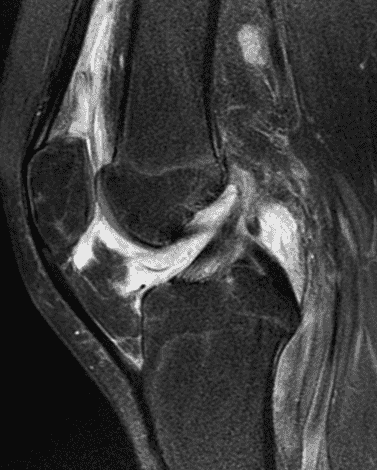

A 19 year-old woman complains of 9 months of unilateral right knee pain and persistent knee swelling without known injury or systemic symptoms. Coronal (1A), sagittal (1B), and transverse (1C) fat-suppressed T2-weighted images of the right knee are provided. What are the findings? What is your differential diagnosis?

Figure 2: (2A) The coronal image shows a large effusion and severe hypertrophic synovitis (asterisks) in the knee. (2B) On the sagittal image the hypertrophic synovium (asterisks) involves the suprapatellar and infrapatellar recesses as well as the anterior and posterior intercondylar notch. A reactive lymph node (arrow) is present in the popliteal fossa. (2C) The axial image demonstrates myositis (arrows) involving the popliteus and peroneus longus muscles. Note the preserved articular cartilage, lack of erosions, and the absence of subcutaneous or marrow edema.